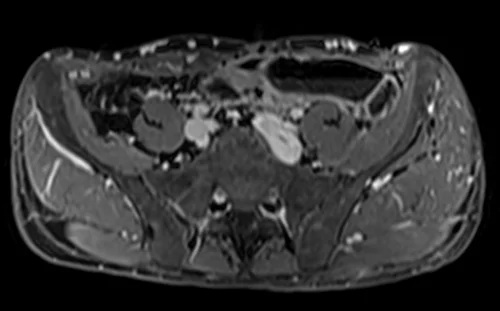

MRV abdomen axial t1 flash post contrast image 7 - MRI